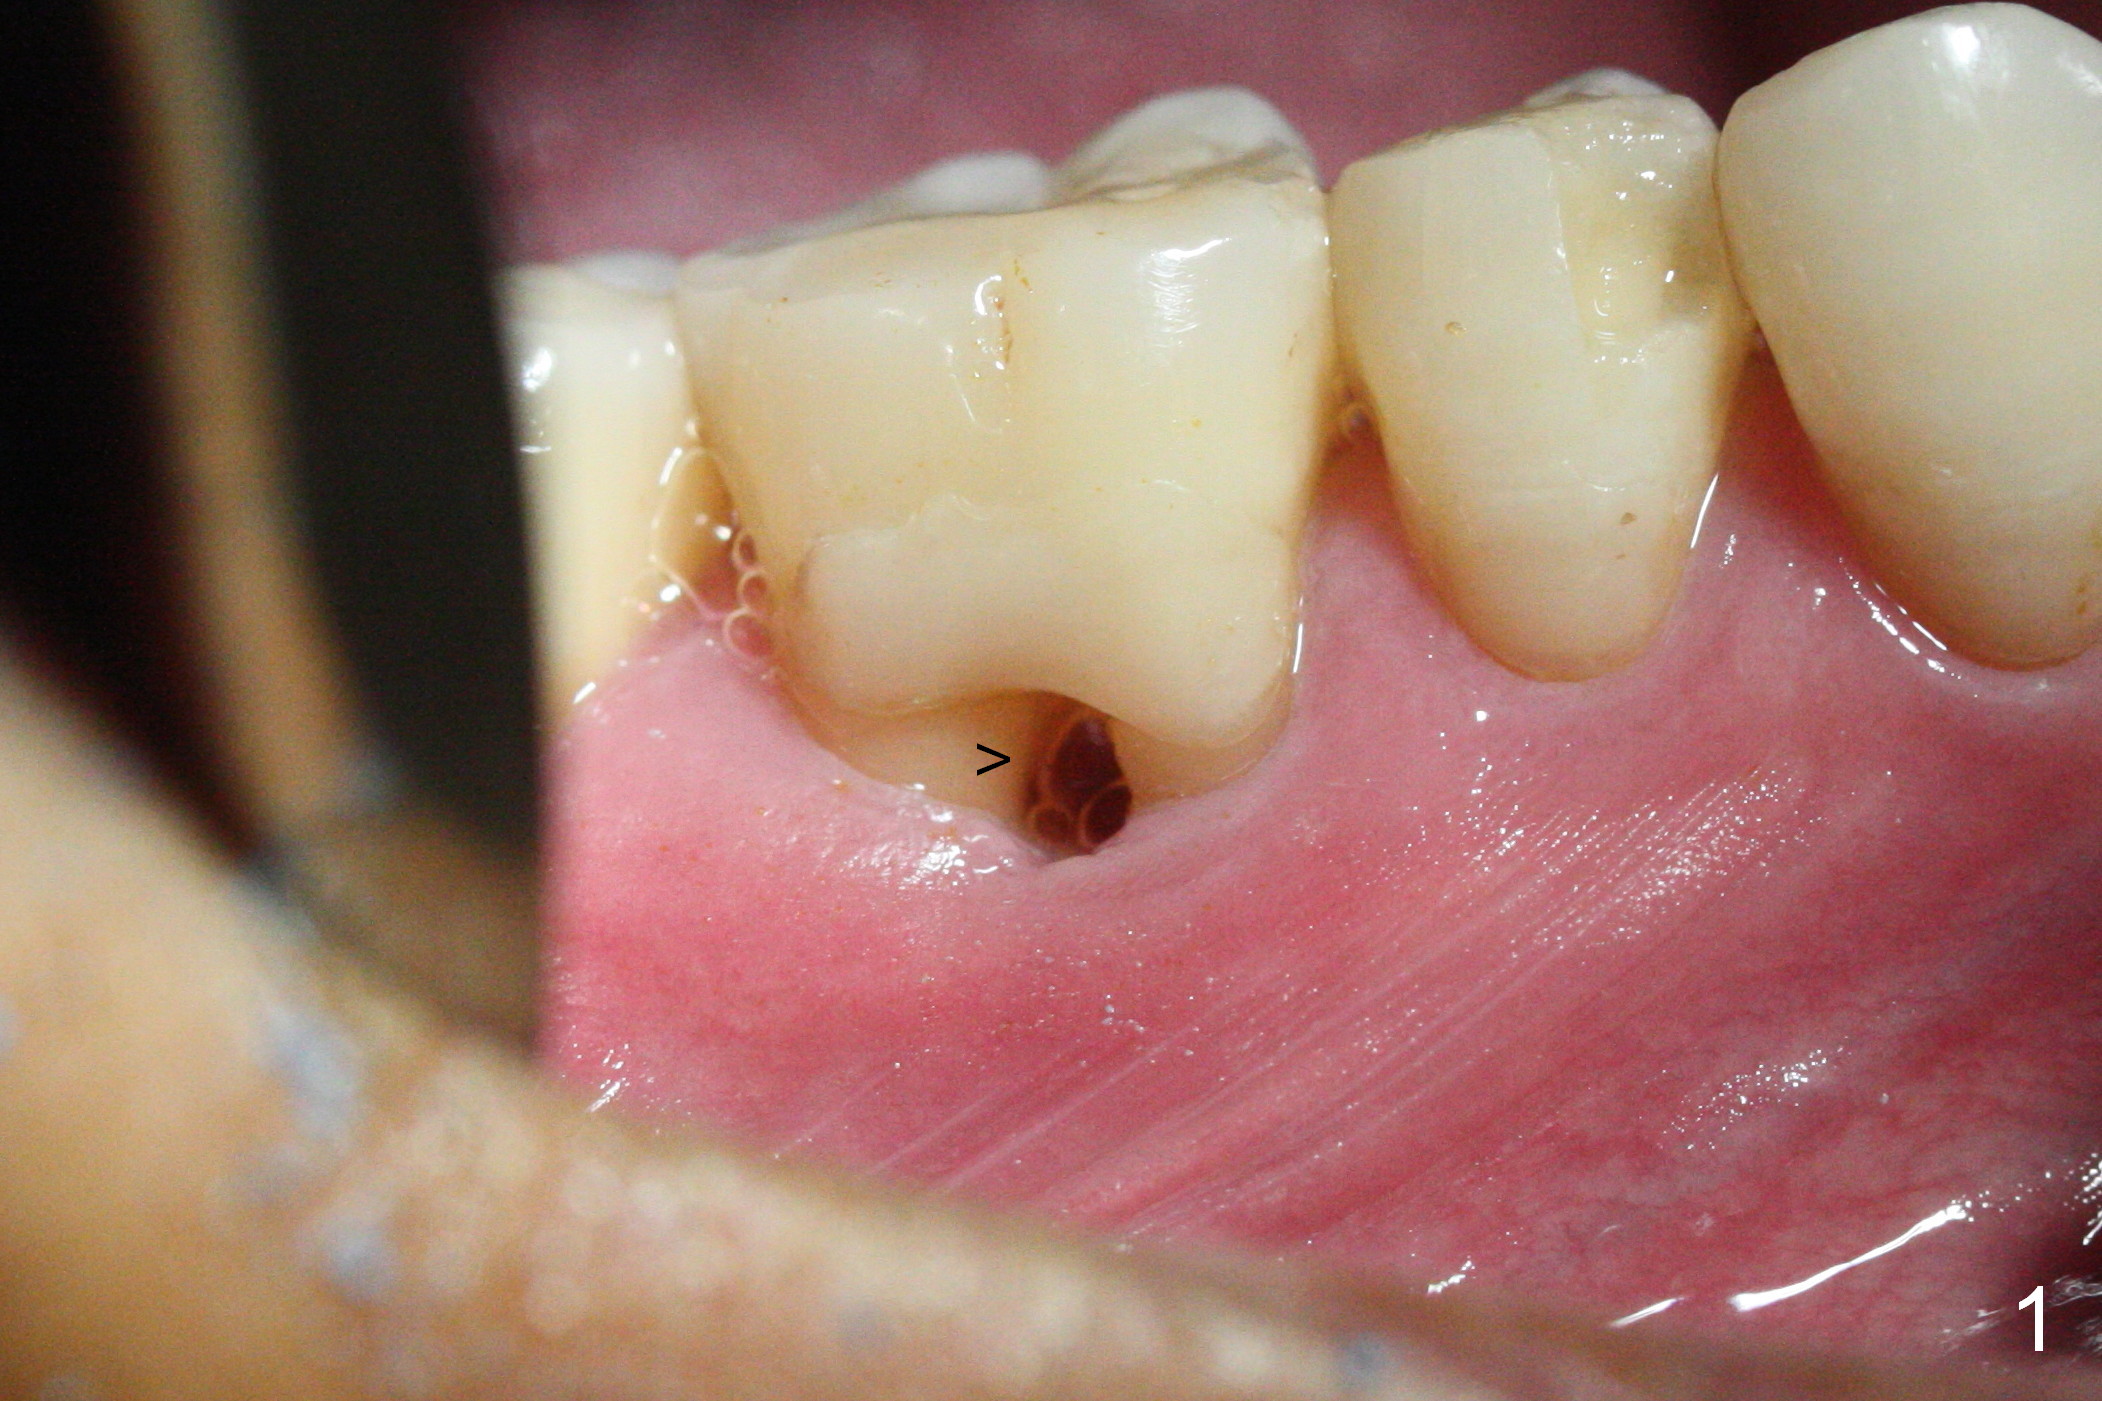

After extraction of the tooth #30 with Class V furcation involvement (Fig.1 (>),2 (L: lingual)), initial osteotomy depth is 8 mm with infiltration anesthesia, but a parallel pin is able to be inserted for 16 mm without pain (Fig.3). There is oozing from the osteotomy. Osteotomy increases in diameter with depth at 8 mm (Fig.4 (3.8 mm drill),5 (5.3 mm tap)). As the Inferior Alveolar Canal (IAC) is indistinct with increased pain during osteotomy, a 5.9x6 mm implant is placed with >50 Ncm following Septocaine infiltration (Fig.6). When bone graft (Fig.7 *) and 7.8x5.5(6) mm abutment (Fig.7,8) are placed, panoramic X-ray is taken (Fig.9). There appears to be a thick layer of spongy bone in the posterior mandible between the red and yellow dashed lines (Fig.5,9). Panoramic X-ray and/or CBCT should be taken if preop PA does not reveal IAC. This patient seems to be a bruxer. There are mandibular tori. Bone loss (furcation involvement) is not proportional to his oral hygiene status. Functional loading (progressive) should be delayed due to bruxism and the short implant.